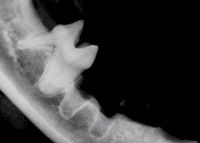

Photo 4: A postoperative radiograph of the patient from Photo 2. Treatment for tooth 408 is complete extraction (Type 1). Treatment for tooth 407 is crown amputation and intentional root retention (Type 2).

Tooth roots classified as undergoing Type 1 resorption require the removal of the entire tooth root and crown by using traditional extraction techniques (Photo 4). Tooth roots for which no periodontal ligament space is readily detected and where no periodontal bone destruction or periapical lucencies exist may be treated by crown amputation and intentional root retention. In these cases, a conservative periodontal flap exposes the marginal extent of the tooth (Photo 5), and a round carbide or diamond bur on a water-cooled, high-speed handpiece is used to remove the crown and contour the bone (Photo 6) before closure with 5-0 absorbable suture (Photo 7).